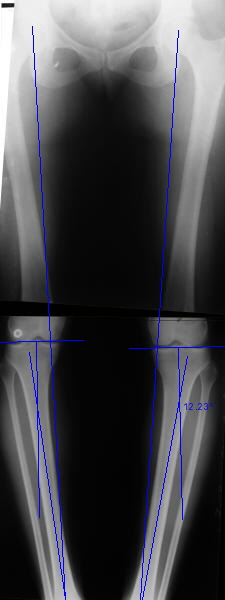

Отправитель: T. Derek V. Cooke 13 Сентябрь 2005, 23:51

|

Hello Alex:

Thanks for the clinical photo.

Your patient appears to have "Insquinting Knees"?

I am attaching a word doc with a 'print screen' of the program in use, showing the images being viewed and analysed

. On the right leg you can see some of the tools (from the tool bar above) applied to demonstrate a mild mech-axis varus of about 5 degrees.

On the left the bone landmarks used in the anlaysis are shown.

The data for the analysis are in the XLs sheet below, exported from the program automatically.

I have given a label of the abreviations and some normative values.

In essence she has a mild mech-axis varus of 7 degrees with some contribution from the femur (2) degrees and more from the tibia (6 degrees), none from the joint.

The analysis took about 6 mins.

Regards

Derek

Отправитель: Alexander Chelnokov 14 Сентябрь 2005, 00:00

TDVC> Your patient appears to have "Insquinting Knees"?

Exactly.

TDVC> In essence she has a mild mech-axis varus of 7 degrees

TDVC> with some contribution from the femur (2) degrees and more from

TDVC> the tibia (6 degrees), none from the joint.

And what is conclusion? Should it be corrected, by what means, at what level, to what axis, with what lateral/medial translation?

Can the attached result be analyzed by the software?

Re: Деформация голеней

Alexander Chelnokov 13 Сентябрь 2005, 23:23

Операция была интересной, много полезного опыта приобрел.

Снимки в приложении - фас сравнительный с неоперированной ногой. Жду критики.

Впрос про остеотомию большеберцовой непраздный. Эта получилась при надломе несколько более наклонно, чем я делал (сейчас проблема,

как на второй ноге сделать так же). Вот этот высоящий "зуб" центрального отломка не заменит ли в плане косметики то, что получается при медиализации дистального?

Отправитель: T. Derek V. Cooke 14 Сентябрь 2005, 18:23

Hi Alex:

Nice job!

It is very interesting to me that as you have derotated the tibia you have centred the patella, I think and the prox tibia looks much more anatomic.

The analysis in the attached images is direct, just using the tools.

Tibial tilt is perhaps more than you want but the tibial correction is to 90 (very slight over

correction.

Will need full length views to tell us about the hka but it appears neutral.

Measurements took 4 mins